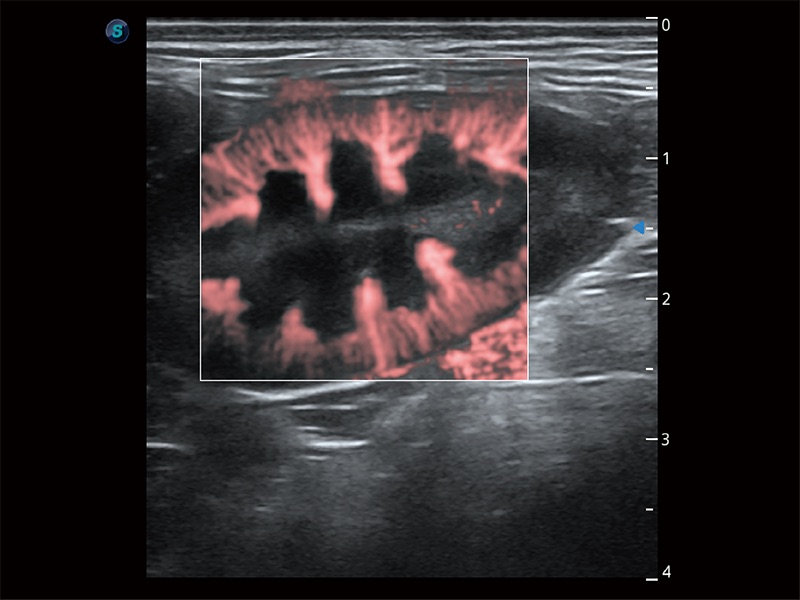

非线性融合造影成像充分利用谐波和基波信号,为难以观察的血流进行增强显像。可用于线阵、凸阵、微凸阵、相控阵探头。

为精细结构及组织边缘提供高清晰度的图像和更大的成像视野。帮助减轻医生的用眼疲劳,快速精准获得测量的数据。

ProPet 80 全新的动物超声智能软件和丰富的探头群,为动物医生提供了高清晰度和精细分辨率的图像,无论在宠物、马科、畜牧还是实验室动物等应用中都可以轻松应对,为您的日常工作带来满意的体验。